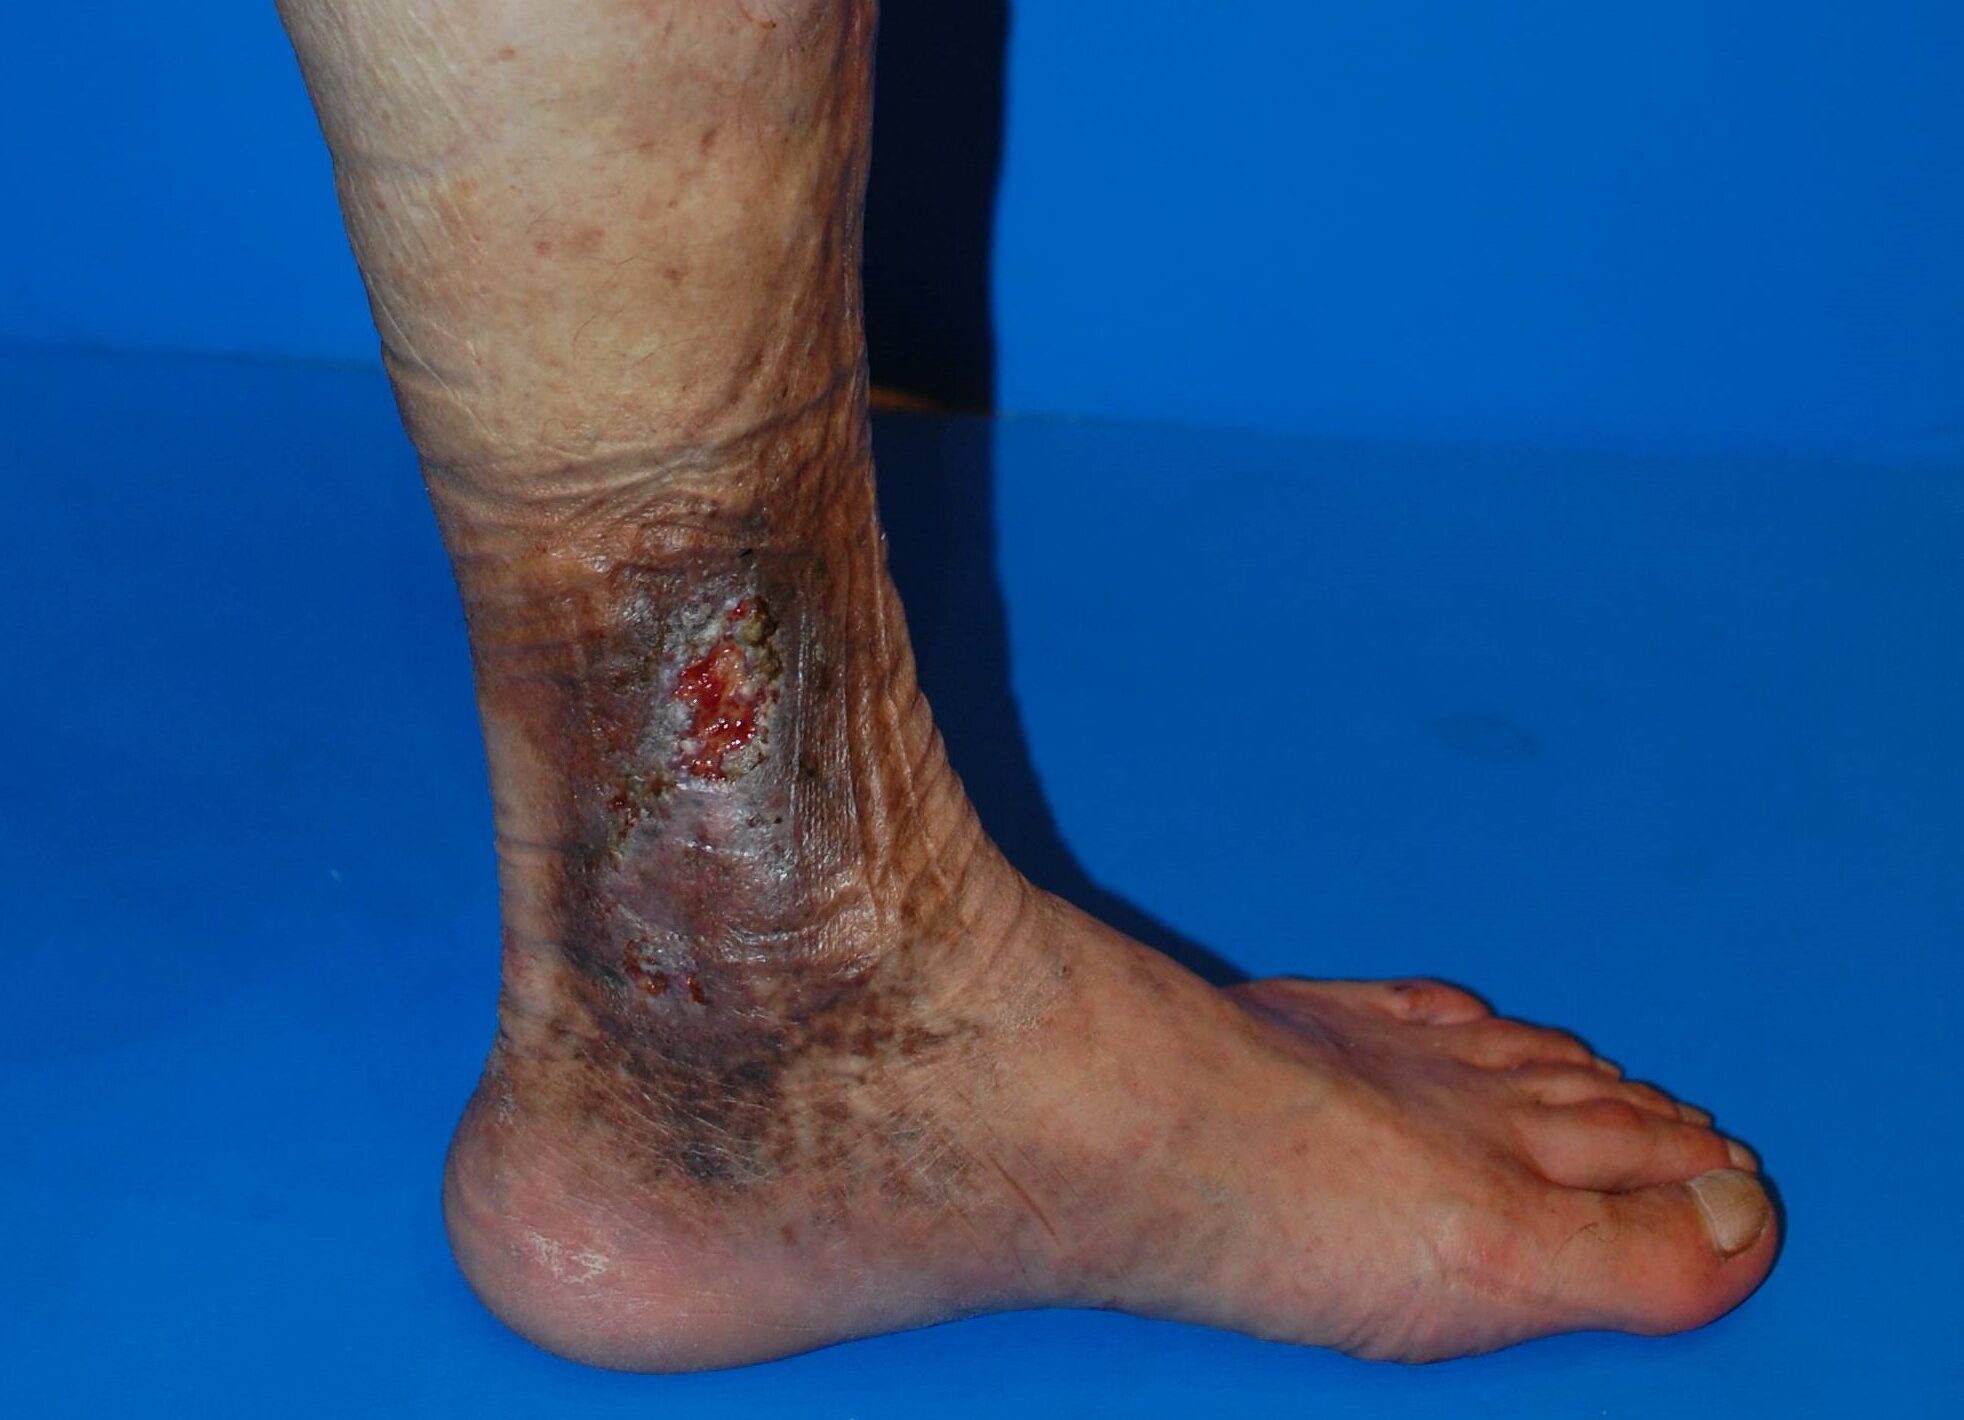

サイン3:血管の周りにしこり・硬さ・傷(潰瘍)がある

- ボコボコした血管の一部が硬く、押すと痛い

- 足首周囲に治りにくいジュクジュクした傷がある

皮膚潰瘍 写真

血栓性静脈炎

これは血栓性静脈炎や下腿潰瘍といった合併症が出ているサインで、

明らかに「様子を見る段階」ではありません。